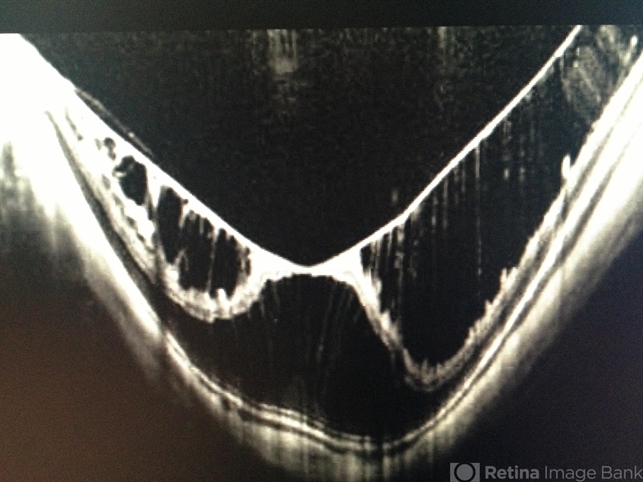

- macular schisis

- SD-OCT image of macular schisis in the left eye of a 46-year-old female who is a -13D myope. Vision was 20/64.